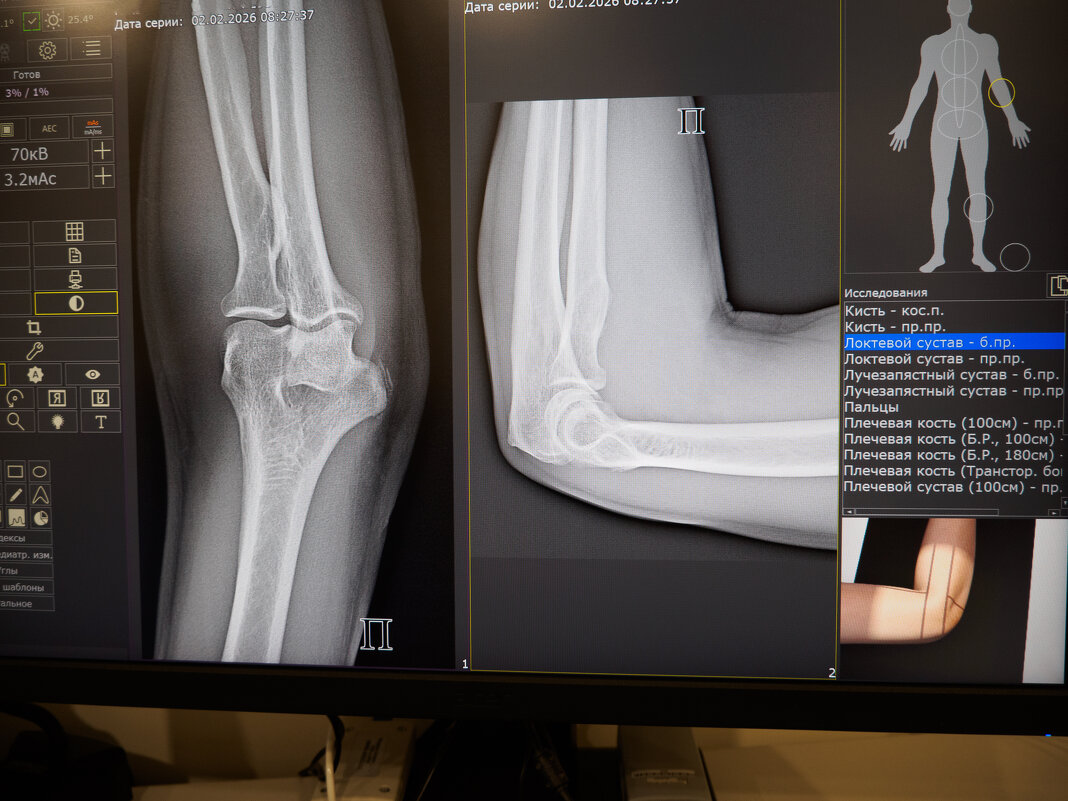

Фото на память. - Как в кино шел,упал не терял сознание,а переломчик есть.

Пока все снимки одной рукой.